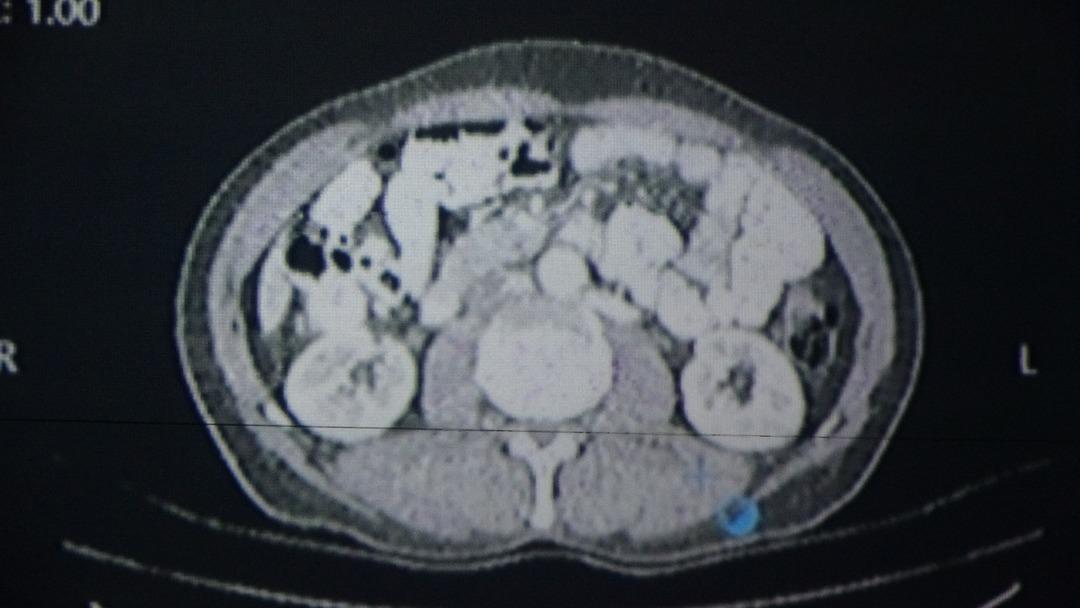

Çalışmada örnek vakalardan biri olarak, Ericiş bölgesinde yaşayan 56 yıllık Sabri SaruylediZ değerlendirildi. Yapay zeka tarafından desteklenen yazılım tarafından önerilen tedavi planı, doktorların kararlarıyla uygulanmıştır. Sarıyız, bu yol sayesinde başarılı cerrahi operasyon sağlığı kazandı.

Sabri Sarıyizz, “Önce kemoterapi ve radyoterapi gördüm. Gıdada bir kitle vardı. Öğretmenimize başvurduğum genel cerrahi uzmanı Prof. Dr. Sebahattin Celik.